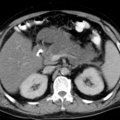

• 假性胰腺囊肿CT

• 急性胰腺炎图4

• 急性胰腺炎图3

• 急性胰腺炎图2

• 急性胰腺炎图1

• 急性胰腺炎